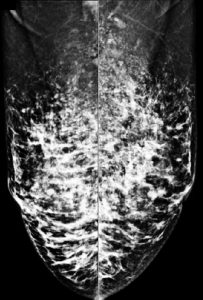

三、乳房MRI磁振造影檢查

無輻射、高解析度、無痛的高階影像檢查,對偵測腫塊病灶有極高的靈敏度,是極佳的診斷利器。

適用對象:有乳癌家族史、曾罹患卵巢癌及子宮內膜癌者、帶有特定家族遺傳基因(BRCA1、BRCA2等)等高危險族群,以及曾接受乳房手術的女性(如自體脂肪豐胸、假體植入),建議至少每2年做一次MRI檢測,除偵測早期乳癌外,同時可評估植入物之完整性。

【個案分享】

64歲石小姐,曾接受矽膠注射隆乳(小針美容),因右側乳房疼痛而求診,但因矽膠隆乳者在乳房攝影(圖A)及超音波下會遮蔽病灶而無法診斷,因此進一步安排磁振造影MRI(圖B)發現:右側乳房有一不規則狀的腫塊(約55mm),併有右側乳頭內縮,高度懷疑惡性腫瘤,經手術證實為乳癌。

(A)

(B)